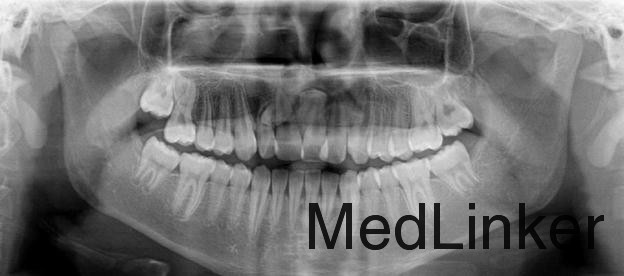

患者,男,拍牙片偶然发现前牙多生牙要求拔除,平素体质一般,无药物、食物过敏史,无高血压、心脏病等系统病史。

曲面断层片和牙科CT检查